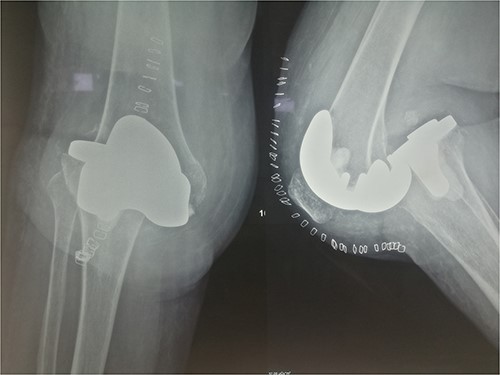

The patient was reoperated, where a more extensive release of the hamstrings was performed, obtaining full extension. The knee was stabilized using a lateral external fixator (Fig. 5). Muscle biopsies were obtained, indicating signs of chronic inflammation. Full weight bearing, using a walker, was permitted from the first postoperative day without substantial complaints.

The external fixator was removed after 6 weeks (Fig. 6), and physical therapy was initiated. The patient’s postoperative course was uncomplicated. One week upon removal, 0°–80° of flexion was achieved through everyday kinesiotherapy. On her last visit, 1 year postoperatively, the patient was ambulatory, with knee ROM of 0°–100° (Fig. 7). No further abnormal neuromuscular signs were observed.